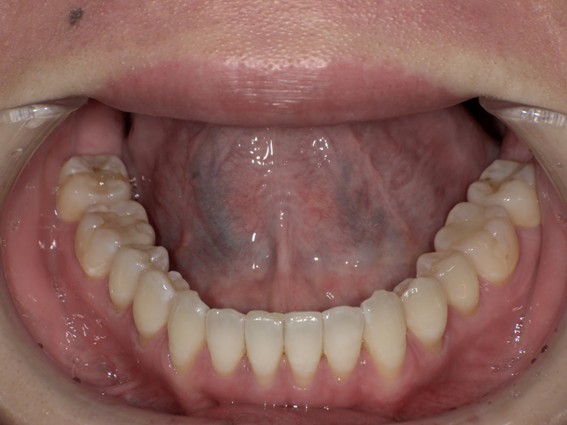

| 主訴 | 前歯が逆に噛んでいる。 |

| 治療内容 | 表側ワイヤー矯正、ジルコニア補綴を行いました。 |

| 治療費 | ワイヤー矯正660,000円(税込) ジルコニア176,000円(88,000円×2歯)(税込) |

| 治療期間 | 30ヶ月 |

| 治療回数 | 30回 |

| 想定されたリスク | 歯根吸収、歯髄壊死、歯髄充血、歯肉退縮のリスクがありました。 |

骨格性Ⅲ級・前歯部反対咬合の症例でした。反対咬合のまま治療していた前歯のサイズ不調和を、表側ワイヤー矯正とプロビジョナルクラウンで調整。正中を整え、犬歯・臼歯ともⅠ級、適切なオーバージェット(上下前歯の前後的な距離)・オーバーバイト(上下前歯の垂直的な重なり)に仕上げました。